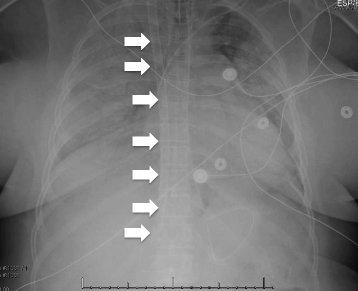

Extracorporeal membrane oxygenation (ECMO) is a mode of extracorporeal life support that augments oxygenation, ventilation and/or cardiac output via cannulae connected to a circuit that pumps blood through an oxygenator and back into the patient. ECMO has been used for decades to support cardiopulmonary disease refractory to conventional therapy. While not robust, there are promising data for the use of ECMO in acute hypoxemic respiratory failure, cardiac arrest, and cardiogenic shock and the potential indications for ECMO continue to increase. This review discusses the existing literature on the potential use of ECMO in critically ill patients within the emergency department.